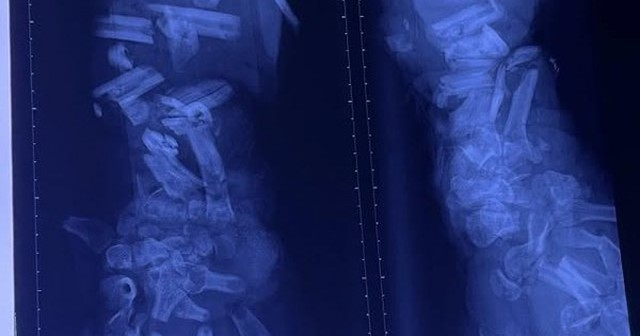

Hình ảnh phim X - quang cho thấy xương cẳng tay và bàn tay trái của bệnh nhân bị gãy từng khúc, không còn hình dạng của xương quay và xương trụ

Bệnh nhân đến cấp cứu với tình trạng vết thương dập nát phức tạp rất nặng cánh tay trái (từ cẳng tay đến bàn tay) do máy nghiền vỏ dừa. Xương tay nát đứt nhiều khúc, mô mềm dập nát nặng, tím tái, dính nhiều đất cát và dầu nhớt. Vì tổn thương quá nặng và không thể cứu được cánh tay nên bác sĩ buộc phải làm mỏm cụt ngang khuỷu tay trái.